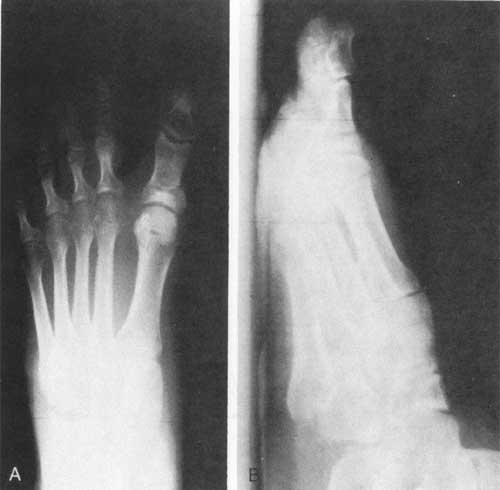

Figure 4

- Preoperatibe view of a patient with PASA deformity.

- The same patient 2 years after an unsuccessful modified McBride-Akin procedure. The surgery failed to correct PASA.

- The successful correction of the PASA with the Isham osteotomy can be seen in this radiograph taken 5 years after surgery.